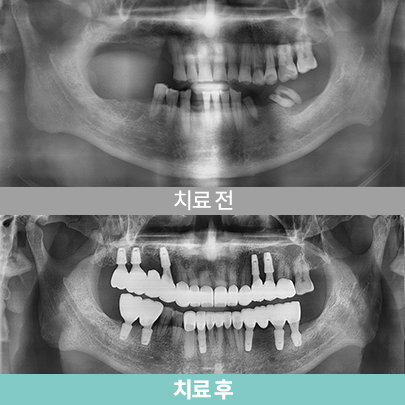

- 80대 여성, 치료 후 4개월

- 심미보철

- 심미보철

- 상악 하이브리드 임플란트

- 80대 여성, 치료 후 4개월

- 심미보철

- 심미보철

- 상악 하이브리드 임플란트